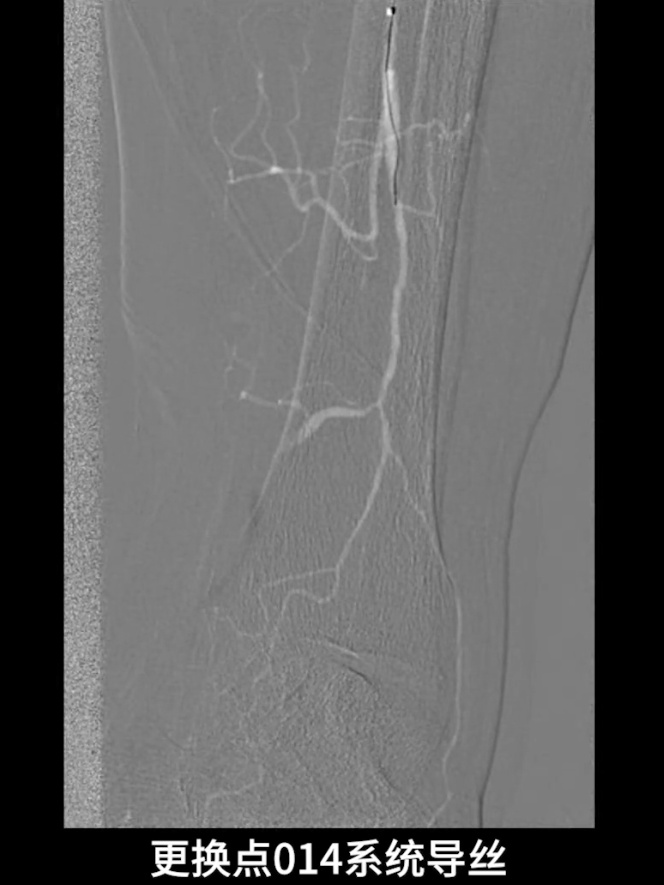

逆穿技术应用:改为逆穿胫后动脉远端,支撑导管配合V18导丝经交通支逆行进入腓动脉远端,逐步推送导丝导管通过胫腓干闭塞段,直至腘动脉近端真腔,与近端导管完成对接,建立膝下流出道操作轨道。

流出道扩张与优化:使用3.0×200mm PTA球囊对“胫腓干-腓动脉”全程进行扩张;

更换0.014系统导丝,经交通支选入胫后动脉远端,